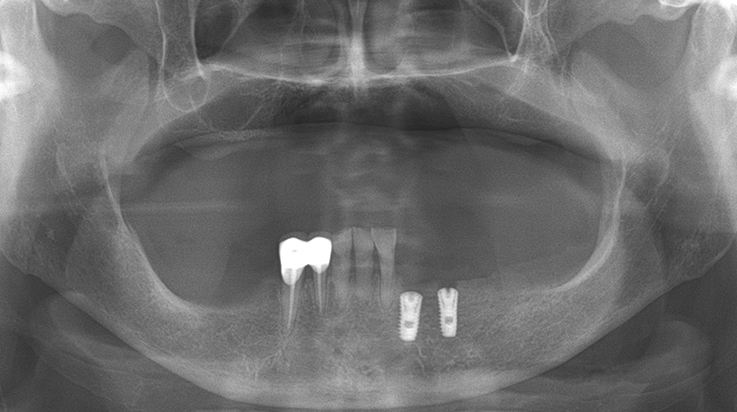

Fully edentulous clinical cases